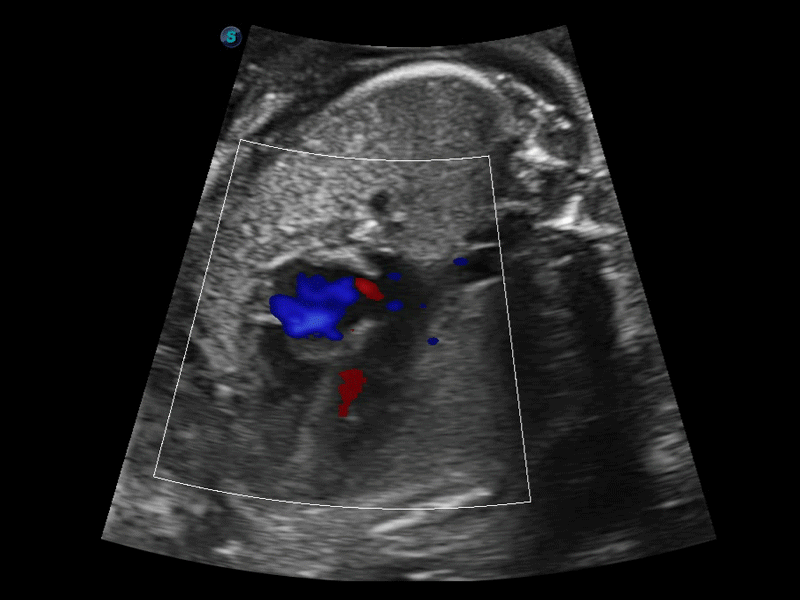

凭借狗万官方网站先进的成像技术和优异的探头技术提供的清晰的图像表现,您可以更自信地做出临床决策。